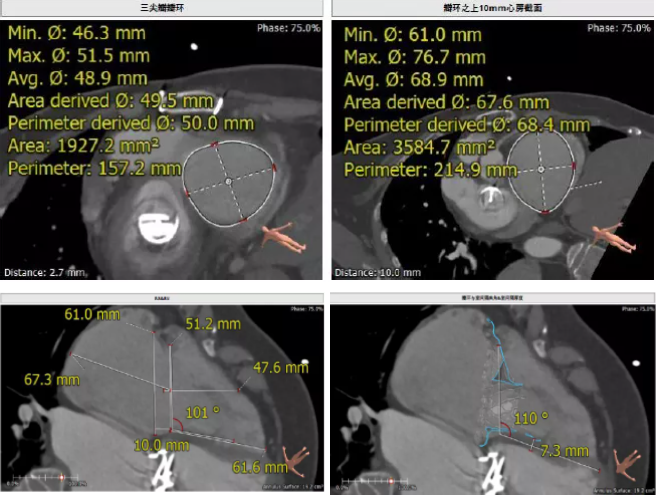

患者64歲女性,18年前接受了“正中開胸二尖瓣機(jī)械瓣置換術(shù)”,2年前超聲檢查發(fā)現(xiàn)“三尖瓣重度返流”。輾轉(zhuǎn)多地,嘗試各種治療方式,均無明顯改善。由于存在相關(guān)合并癥,傳統(tǒng)外科手術(shù)風(fēng)險(xiǎn)大,郭惠明教授團(tuán)隊(duì)結(jié)合該患者CT、超聲檢查結(jié)果,對(duì)該患者的情況進(jìn)行了充分的評(píng)估和討論,決定采用LuX-Valve人工三尖瓣介入瓣膜置換系統(tǒng)對(duì)患者進(jìn)行微創(chuàng)介入治療,以最小的創(chuàng)傷解決患者的病痛。

術(shù)前CT評(píng)估